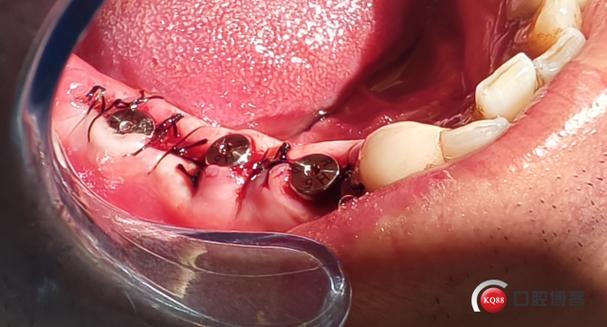

种植体植入与初期稳定性评估

选择直径与拔牙窝匹配的种植体(通常直径3.5-4.5mm,长度10-13mm),通过外科导板引导,以35-45°角度植入牙槽骨,确保种植体顶端位于牙槽骨嵴下1-2mm,避免穿出牙槽骨唇侧壁(影响前牙美观),植入后使用扭矩扳手检测初期稳定性,若扭矩值≥35Ncm,表明种植体与骨组织达到良好机械嵌合,可进行即刻修复;若稳定性不足,需延期种植或植骨后二期植入。